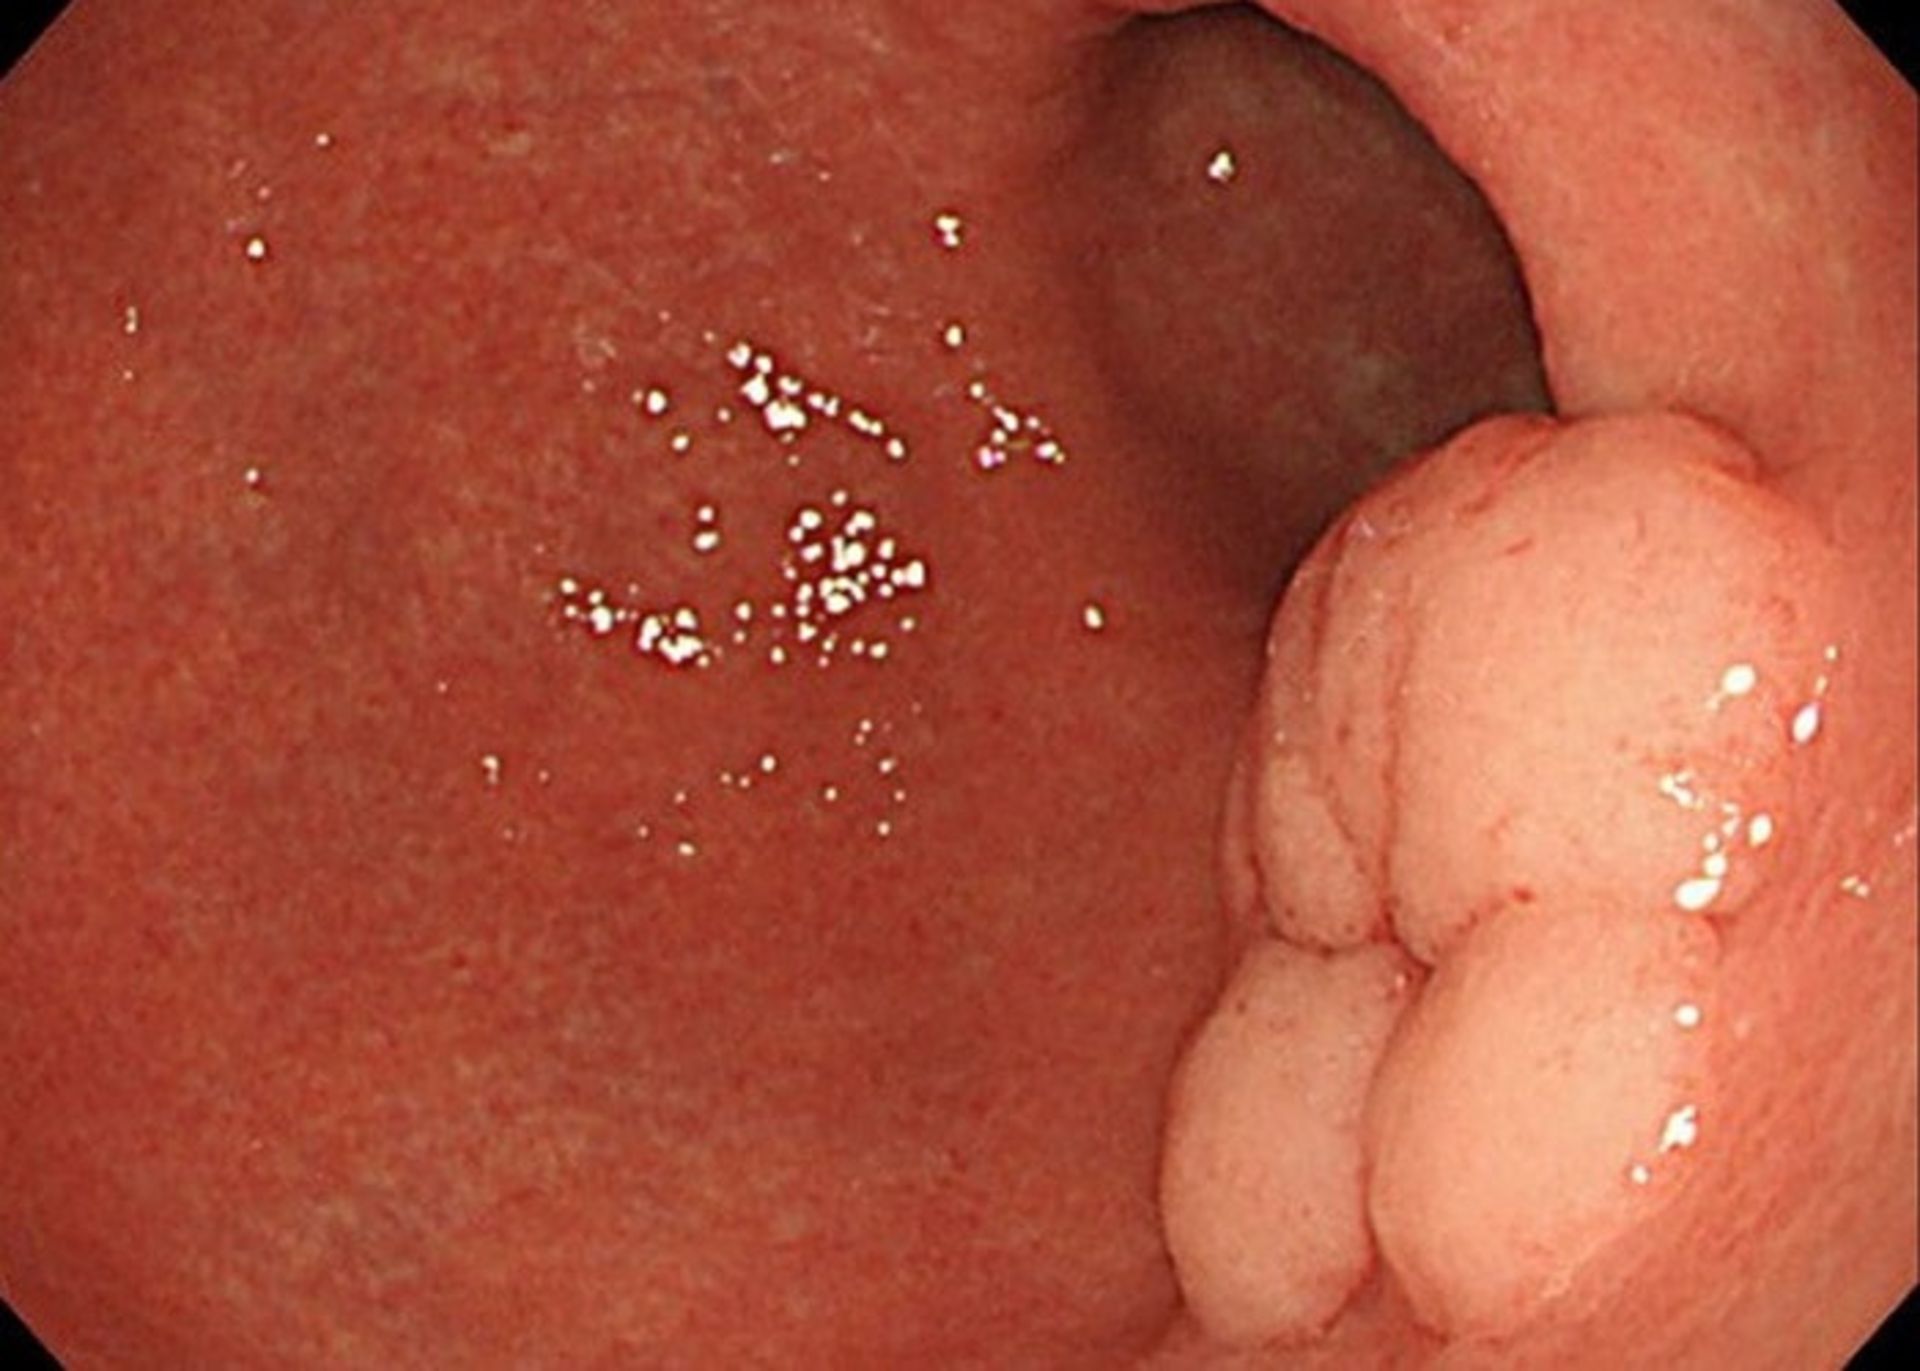

آندوسکوپی فوقانی: آندوسکوپی فوقانی یا EGD آزمایش اصلی تشخیص سرطان معده است. در این آزمایش، پزشک یک آندوسکوپ را که یک لولهی نازک دارای منبع نور و یک دوربین ویدئویی کوچک است، از راه گلو وارد معدهی فرد بیمار میکند. با این کار پزشک میتواند پوشش مری، معده و بخش ابتدایی رودهی کوچک را ببیند. اگر مناطق غیرطبیعی مشاهده شوند، با استفاده از ابزاری که به آندوسکوپ متصل است، نمونهبرداری انجام میشود. این نمونهها به آزمایشگاه فرستاده میشوند و با استفاده از میکروسکوپ مشخص میشود که آیا سلولهای سرطانی وجود دارند یا خیر. با استفاده از آندوسکوپ، سرطان معده میتواند شبیه یک تودهی برآمده یا قارچمانند، یا مناطق ضخیم شده، مسطح و پراکنده از مخاط دیده شود که با عنوان لینیت پلاستیکا شناخته میشوند. سندرم سرطان ارثی منتشرهی معده، اغلب ازطریق آندوسکوپی قابل رویت نیست.

بیوپسی: درصورتیکه ازطریق آندوسکوپ یا تصویربرداری، یک منطقهی غیرطبیعی در معده مشاهده شود، پزشک ممکن است مشکوک به وجود سرطان شود اما تنها راه برای تشخیص نهایی این موضوع انجام یک نمونهبرداری است. در عمل نمونهبرداری پزشک نمونهای از سلولهای منطقهی غیرطبیعی را برمیدارد. نمونهبرداریهایی که با هدف بررسی سرطان معده انجام میشوند، اغلب درجریان آندوسکوپی فوقانی معده گرفته میشوند. اگر پزشک در جریان آندوسکوپی هرگونه منطقهی غیرطبیعی در پوشش معده مشاهده کند، ابزار نمونهبرداری را ازطریق آندوسکوپ وارد معده میکند. برخی از انواع سرطانهای معده میتوانند در عمق دیوارهی معده بروز کنند که این امر موجب میشود نمونهبرداری از آنها با استفاده از روش آندوسکوپی استاندارد دشوار شود. اگر پزشک گمان کند سرطان ممکن است در عمق دیوارهی معده اتفاق افتاده باشد، میتواند از روش اولتراسوند اندوسکوپی برای هدایت سوزن نمونهبرداری به دیوارهی معده استفاده کند. نمونهبرداری همچنین ممکن است از مناطق احتمالی انتشار سرطان مانند گرههای لنفاوی مجاور یا مناطق مشکوک در دیگر قسمتهای بدن انجام شود.